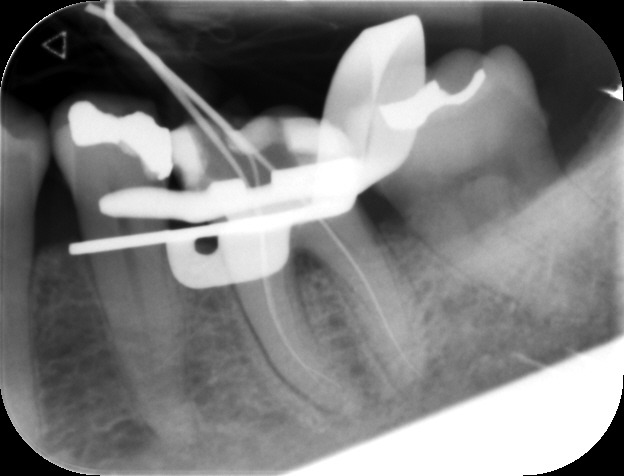

Before commencing the treatment, a local anaesthetic is administered and later a protective non-latex rubber sheet is placed around the tooth to prevent saliva contaminating the tooth and at the same time improves patients comfort.

An access cavity is placed on the surface where the patient bites, to reach the root canals of the tooth. Once all the canals are identified, small files are used to remove the infected pulp.

Files of different sizes are used to eliminate bacteria and infection and to shape the canals. The canals are disinfected thoroughly with irrigants and later the canals will be sealed in 3 dimensions with a special medicament called gutta-percha to prevent reinfection of the tooth and the access cavity will be sealed with a temporary filling.